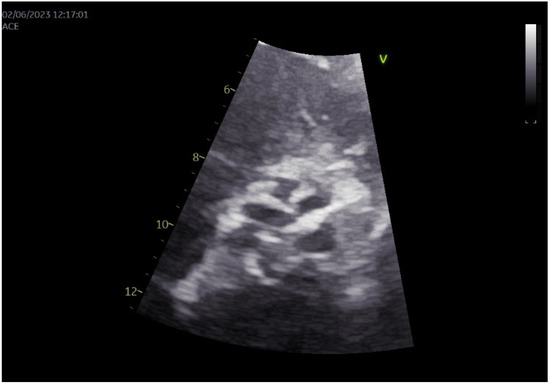

2. Case Presentation

3.8. Our Case